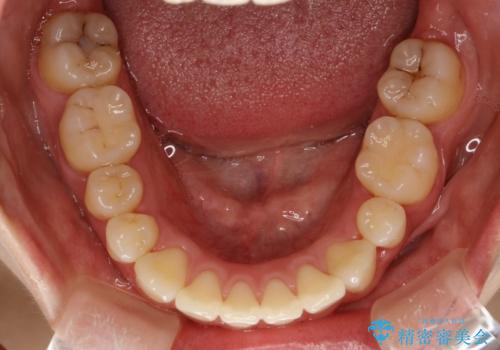

抜歯をして前歯を下げ、ガタつきを取り除く ワイヤー矯正

- 上顎両側第1小臼歯、下顎左側第2小臼歯の3本を抜歯、ラビアルのワイヤー矯正を計画した。

抜歯矯正は抜歯にできたスペースをつかい、前歯を積極的に下げたり、大きなガタつきを取り除くことができますが、その分時間がかかります。